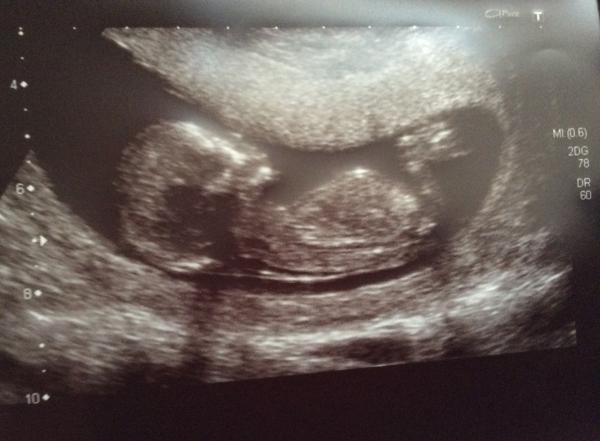

Back from scan and are celebrating with a sausage sandwich.

Have attached picture. Saw baby wombat wriggling and moving around which was lovely. Don't remember DS wriggly so much at his early scans.

Baby is fine. The NT seems fine but have to wait a week until the blood results are back. DP doesn't want to tell anyone till then. Hmm They have also moved my due date forward to 10th November.